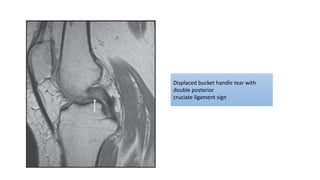

Displaced bucket handle tear with

double posterior

cruciate ligament sign